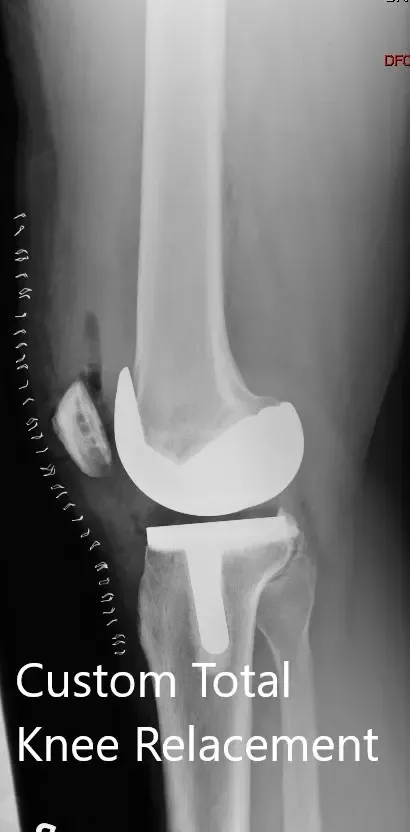

Postoperative X-ray showing the AP view of both knees.